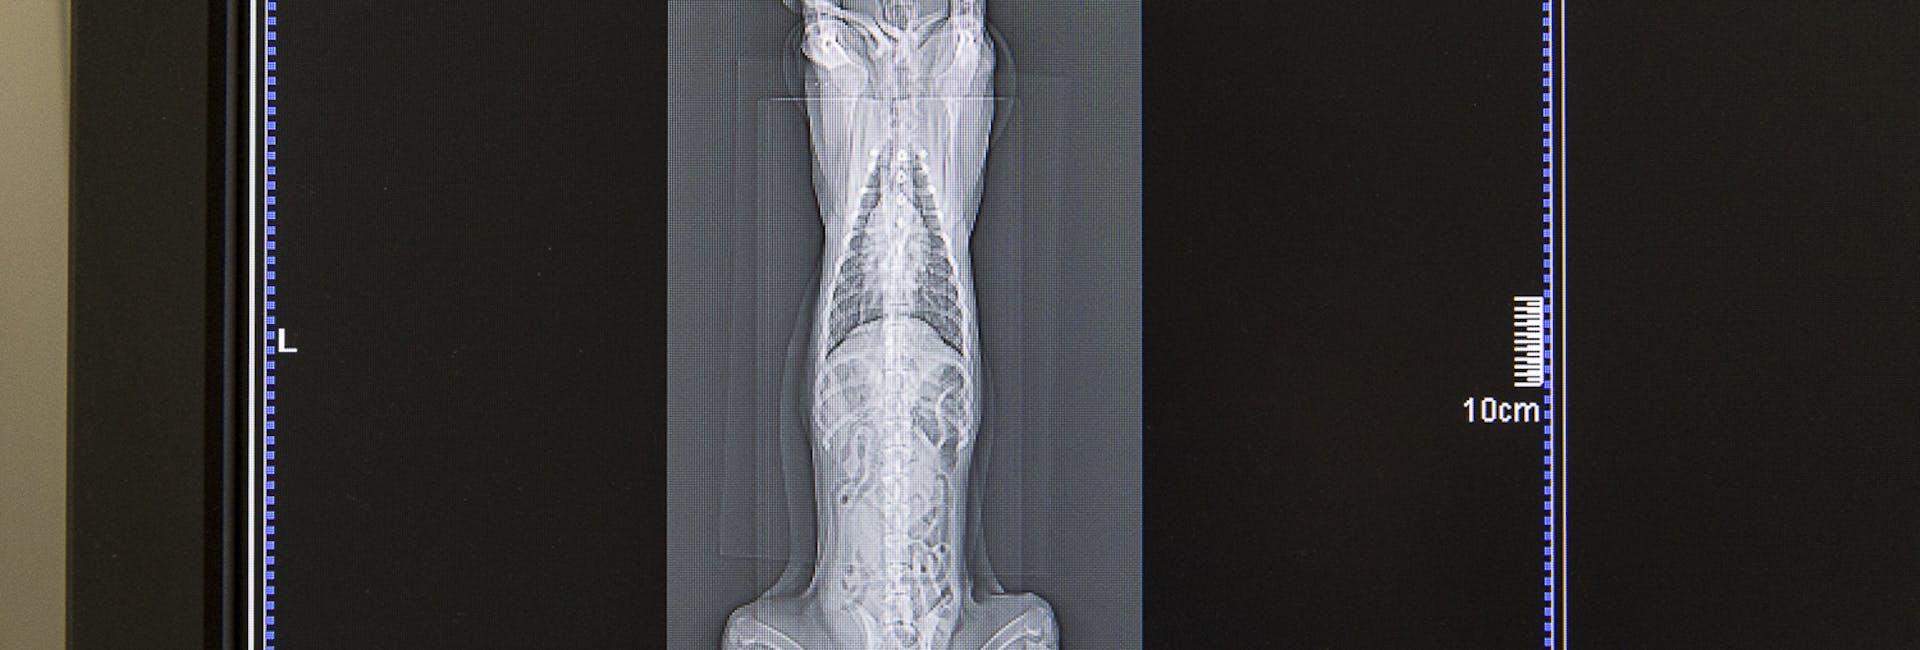

La radiologia in medicina veterinaria è un metodo di indagine finalizzato alla produzione, all'elaborazione e successiva lettura di immagini radiologiche a scopo diagnostico. Questa tecnica consente infatti di esaminare ed accertare le condizioni della morfologia e funzionalità degli organi e dei tessuti del pet in modo rapido e preciso, così da poterne valutare eventuali alterazioni. Lo screening radiologico si basa sull'utilizzo di particolari macchinari che, attraverso l'emissione di una certa quantità di radiazioni, favoriscono la produzione di immagini a scopo diagnostico. Quest’ultime, purché interpretate da personale adeguatamente formato, permetteranno così di formulare una diagnosi affidabile.